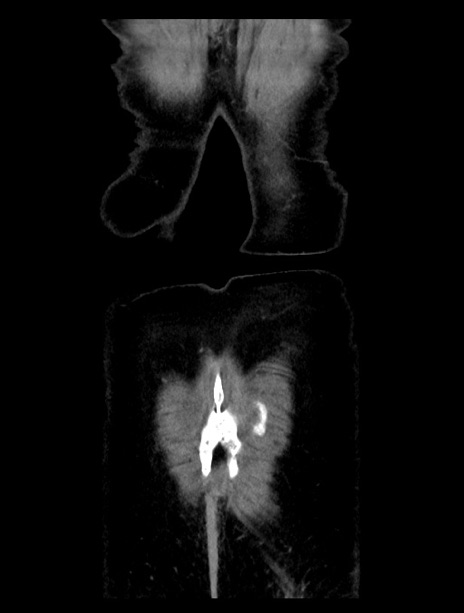

横断像